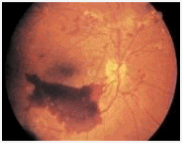

¸Á¸·Ç÷°üÀÌ º¯È­µÇ¾î ÃâÇ÷À» ÀÏÀ¸Å°°í °á±¹¿¡´Â ½É°¢ÇÑ ½Ã·Â Àå¾Ö¸¦ À¯¹ßÇÏ´Â ¹«¼­¿î ÁúȯÀÔ´Ï´Ù. ´ç´¢º´¼º ¸Á¸·ÁõÀº Å©°Ô µÑ·Î ³ª´©¾î ºñÁõ½Ä¼º°ú Áõ½Ä¼ºÀ¸·Î ±¸ºÐÇÕ´Ï´Ù. Áõ½Ä´ç´¢¸Á¸·º´Áõ¿¡¼­ ¸Á¸·ÀÇ ½Å»ýÇ÷°ü°ú À¯¸®Ã¼ ÃâÇ÷ ÀÚ·á : www.myphototv.com ºñÁõ½Ä¼º ¸Á¸·¿°Àº ¸Á¸·Ç÷°ü¿¡ ¿©·¯ ÀÌ»óÀÌ ³ªÅ¸³ªÁö¸¸ ºñ±³Àû Ãʱ⠻óÅ·ΠÁõ»óÀÌ °¡º±°í ´ë·« 80%¿¡¼­ ÁøÇàÇÏÁö ¾Ê½À´Ï´Ù. ºÒÇàÈ÷µµ ¸Á¸· Á߽ɺÎÀ§¿¡ ÀÌ»óÀÌ »ý±â¸é ½Ã·ÂÀå¾Ö°¡ ½É°¢ÇÒ ¼öµµ ÀÖ½À´Ï´Ù. Áõ½Ä¼ºÀ¸·Î ÀÌÇàµÇ´ÂÁö Á¤±âÀû °üÂûÀÌ ÇÊ¿äÇÑ ½Ã±âÀÔ´Ï´Ù.

Áõ½Ä¼º ¸Á¸·¿°Àº ºñÁ¤»óÀûÀÎ »õ·Î¿î Ç÷°üµéÀÌ ÃÊÀÚü(=À¯¸®Ã¼)¶ó´Â ºÎÀ§·Î Áõ½ÄµÇ´Â ¸Å¿ì À§ÇèÇÑ »óÅÂÀÔ´Ï´Ù. ÀÌ Ç÷°üµéÀº ¸Å¿ì ¾àÇϱ⠶§¹®¿¡ ½±°Ô ÆÄ¿­µÇ¾î ÃâÇ÷À» ÀÏÀ¸ÄѼ­ ½Ã·ÂÀ» °¡¸®´Â °Í »Ó¸¸ ¾Æ´Ï¶ó ¹ÝÈç(ÈäÅÍ)Á¶Á÷ÀÌ Çü¼ºµÇ¸é¼­ ¸Á¸·¹Ú¸®¶ó´Â ½É°¢ÇÑ ÇÕº´ÁõÀ» À¯¹ß½ÃÄÑ °á±¹ ½Ç¸í±îÁö À̸£°Ô µË´Ï´Ù. ¶ÇÇÑ ³ì³»ÀåÀ̶ó´Â ÇÕº´Áõµµ Àß ¿À¸ç ¿ª½Ã ½Ç¸íÀ» ÀÏÀ¸Å°°Ô µË´Ï´Ù.